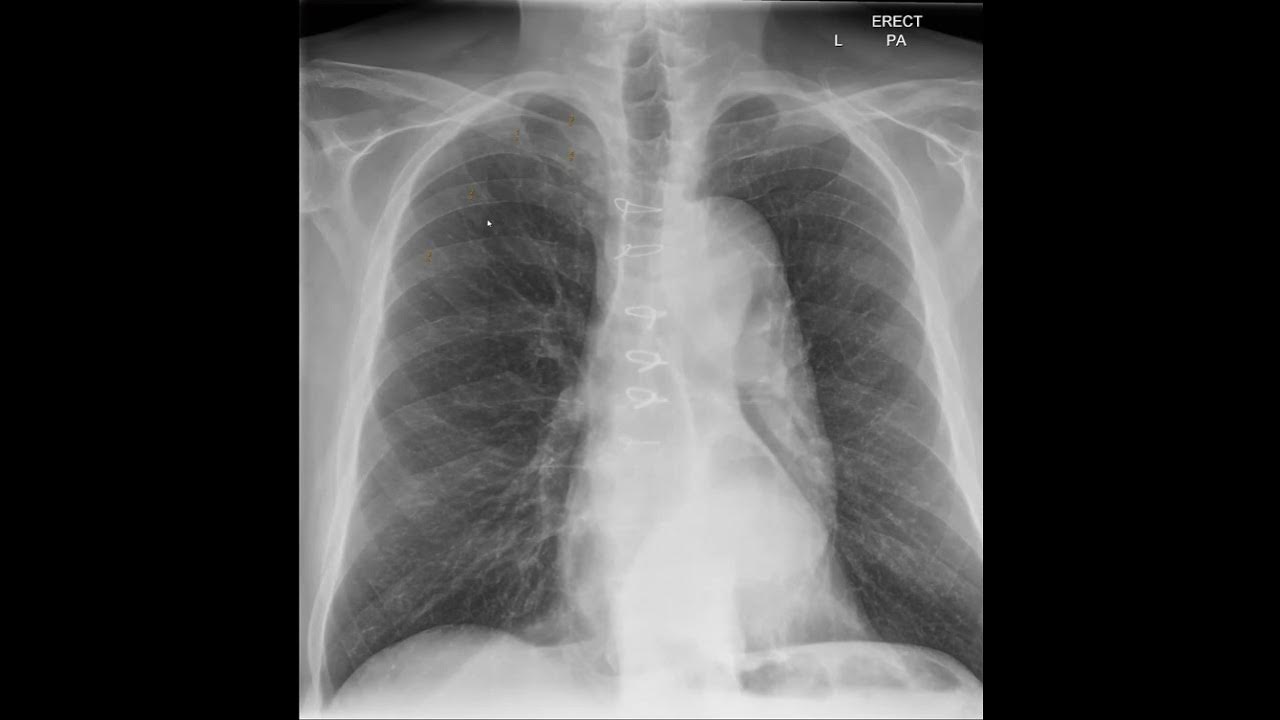

Counting Ribs In Chest X Ray . In this video we'll cover the points of how to count the ribs in a chest x ray and why to? If the broken rib has resulted in a punctured lung and/or intrathoracic bleeding, a pneumothorax (air in the thorax) or hemothorax (blood in the thorax, opacifying. Rib fractures, however, can sometimes be hard to see. The sternum is also included on a frontal view but it overlies other midline structures and so is obscured. The ribs ap view is a specific projection employed in the assessment of the posterior ribs. The front opaque appearing side of ribs is actually its posterior side. Which is one of the most common tasks you'll. You should see 10 to 11 ribs with a good inspiratory effect. But patchy regions of the lung where contusions have been sustained may also be present and should be noted.

The front opaque appearing side of ribs is actually its posterior side. The ribs ap view is a specific projection employed in the assessment of the posterior ribs. Rib fractures, however, can sometimes be hard to see. The sternum is also included on a frontal view but it overlies other midline structures and so is obscured. In this video we'll cover the points of how to count the ribs in a chest x ray and why to? You should see 10 to 11 ribs with a good inspiratory effect. If the broken rib has resulted in a punctured lung and/or intrathoracic bleeding, a pneumothorax (air in the thorax) or hemothorax (blood in the thorax, opacifying. But patchy regions of the lung where contusions have been sustained may also be present and should be noted. Which is one of the most common tasks you'll.